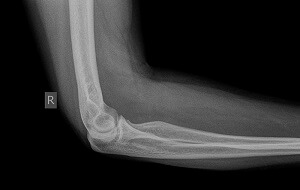

Сломанная кость в этой области не несет особой опасности для жизни, сколько будет срастаться сустав, напрямую будет зависеть от физического состояния и возраста пациента. При переломе головки лучевой кости понадобиться наложить гипс. Лечение длиться от 1 до 3 месяцев. Чем меньше возраст больного, тем быстрее восстановится рука. У пожилых людей восстановление идет медленнее.

Вывих или другие осложнения могут увеличить продолжительность ношения гипса до нескольких месяцев. Хирургическое лечение назначается, если есть отломок: потребуется репозиция для восстановления анатомической целостности кости. Если же смещение исключено, достаточно иммобилизовать конечность на период не более 1,5 месяца. При открытых переломах время ношения гипса зависит от того, какое лечение выбрано.

Врачи отмечают, что лечение перелома головки лучевой кости требует комплексного подхода. В зависимости от характера и степени повреждения, может быть рекомендовано как консервативное, так и хирургическое вмешательство. Консервативное лечение включает иммобилизацию с помощью гипса или шины, что позволяет кости зажить в правильном положении. Хирургическое вмешательство, в свою очередь, может потребоваться при смещении фрагментов или наличии осложнений.

Неосложненные закрытые переломы, лечатся иммобилизацией. Используется гипс, жесткий ортез на руку при переломе лучевой кости или полимерная повязка. После месяца ношения такие повязки снимаются и начинается реабилитация локтевого сустава.